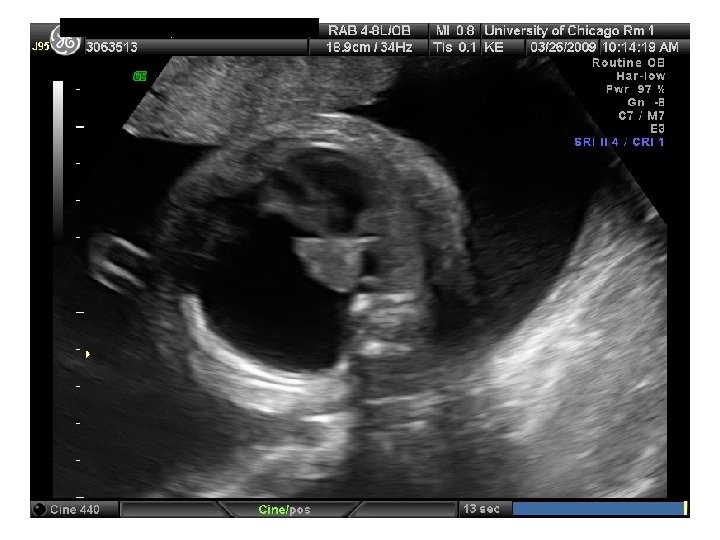

QUIZ What is Your Diagnosis? Case: Patient J. F. 30 years old, at 32 week gestation. Presented with the following pictures.

Answer: a) Trisomy 21 b) Non-immune Hydops c) Paravo virus Infection